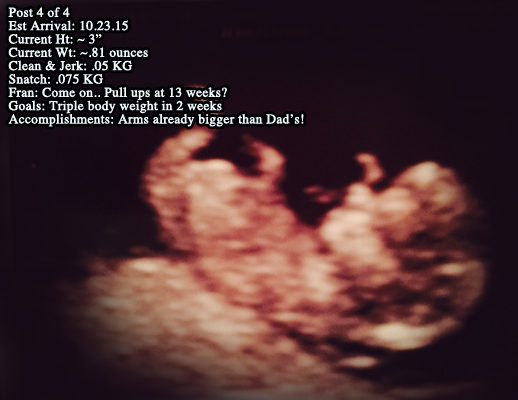

Post 4 of 4 This year we post the attached picture to announce the arrival of…… Coach Merrilee and Coach Daniel’s first…….BABY! (what have we gotten ourselves into?)